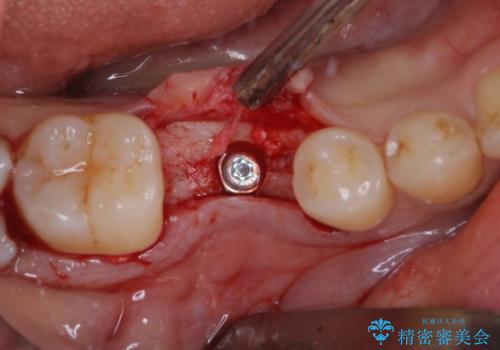

- 大学病院でインプラント治療を進めていたものの、予約のタイミングが合わないとのことで来院された患者様です。

欠損部位の骨や歯肉の状態は非常に良く、速やかにインプラント埋入を行い、補綴治療を進めて行くことのできる状態でした。